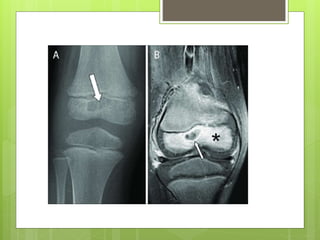

Pathophysiology of hematogenous seeding.When under pressure, exudate

Pattern of spread of infection. From the initial metaphyseal focus, the

Pathophysiology of hematogenousseeding.When under pressure, exudate or abscess can extend through Volkmann canals into subperiosteal region and from there into medullary cavity or epiphysis.

Pattern of spreadof infection. From the initial metaphyseal focus, the infection can spread into the epiphysis, the joint space, the subperiosteal space, the soft tissues, and the shaft of the bone.